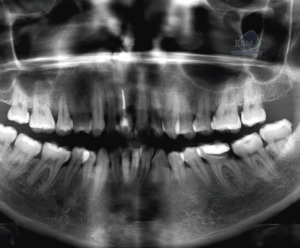

La enfermedad de Paget ocurre con más frecuencia en la pelvis, fémur, cráneo y vértebras y en raras ocasiones en los maxilares. Afecta con mayor frecuencia al maxilar superior. Aunque la enfermedad es bilateral puede existir un solo maxilar afectado. La estructura interna se puede observar en tres estadios, el primero radiolúcido, un segundo estadio granular y el tercero se observa como un estadio aposicional tardío más denso y radiopaco. Las trabéculas suelen estar alteradas en cuanto al número y la forma. La densidad media de los maxilares puede disminuir o aumentar dependiendo del número de trabéculas.